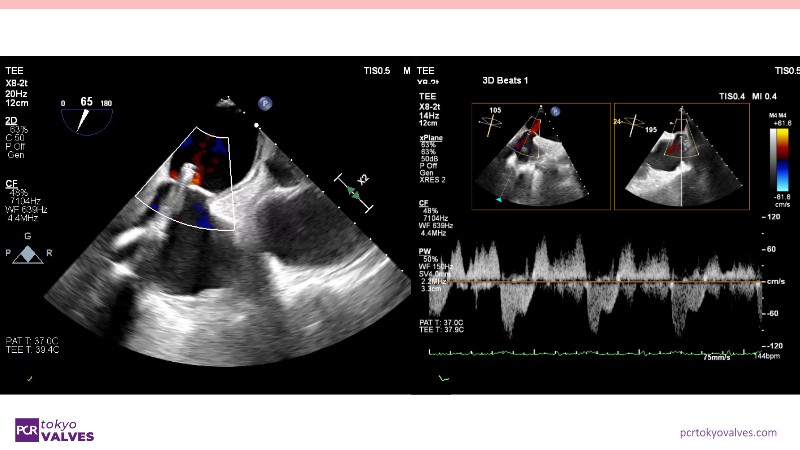

Explore the latest advancements in TEER therapy with this PCR Tokyo Valves 2025 session dedicated to MitraClip. Through expert-led case discussions, gain a deeper understanding of complex scenarios, including restricted posterior leaflet in functional mitral regurgitation, commissure lesion (A3P3), and MitraClip combined with Amulet.

This session also highlights key findings from the OCEAN study, shedding light on 1-year heart failure rehospitalisation outcomes with MitraClip. Additionally, discover how atrioventricular valve morphology impacts treatment strategies and how the four available clip sizes can be used to personalise and optimise TEER outcomes.